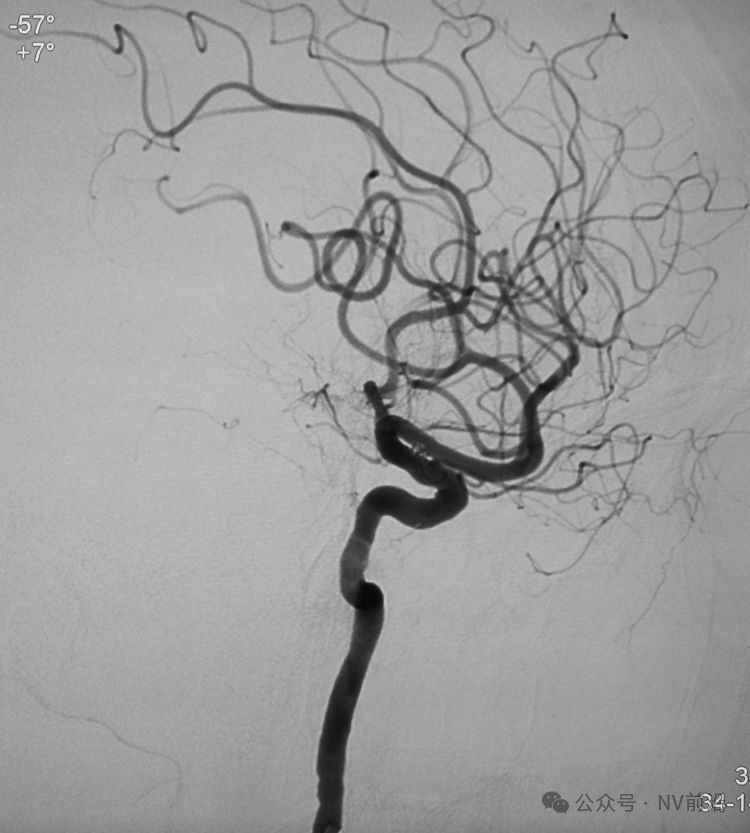

术后左颈内动脉工作位造影和蒙片。

术后左颈内动脉造影三维重建显示动脉瘤消失。